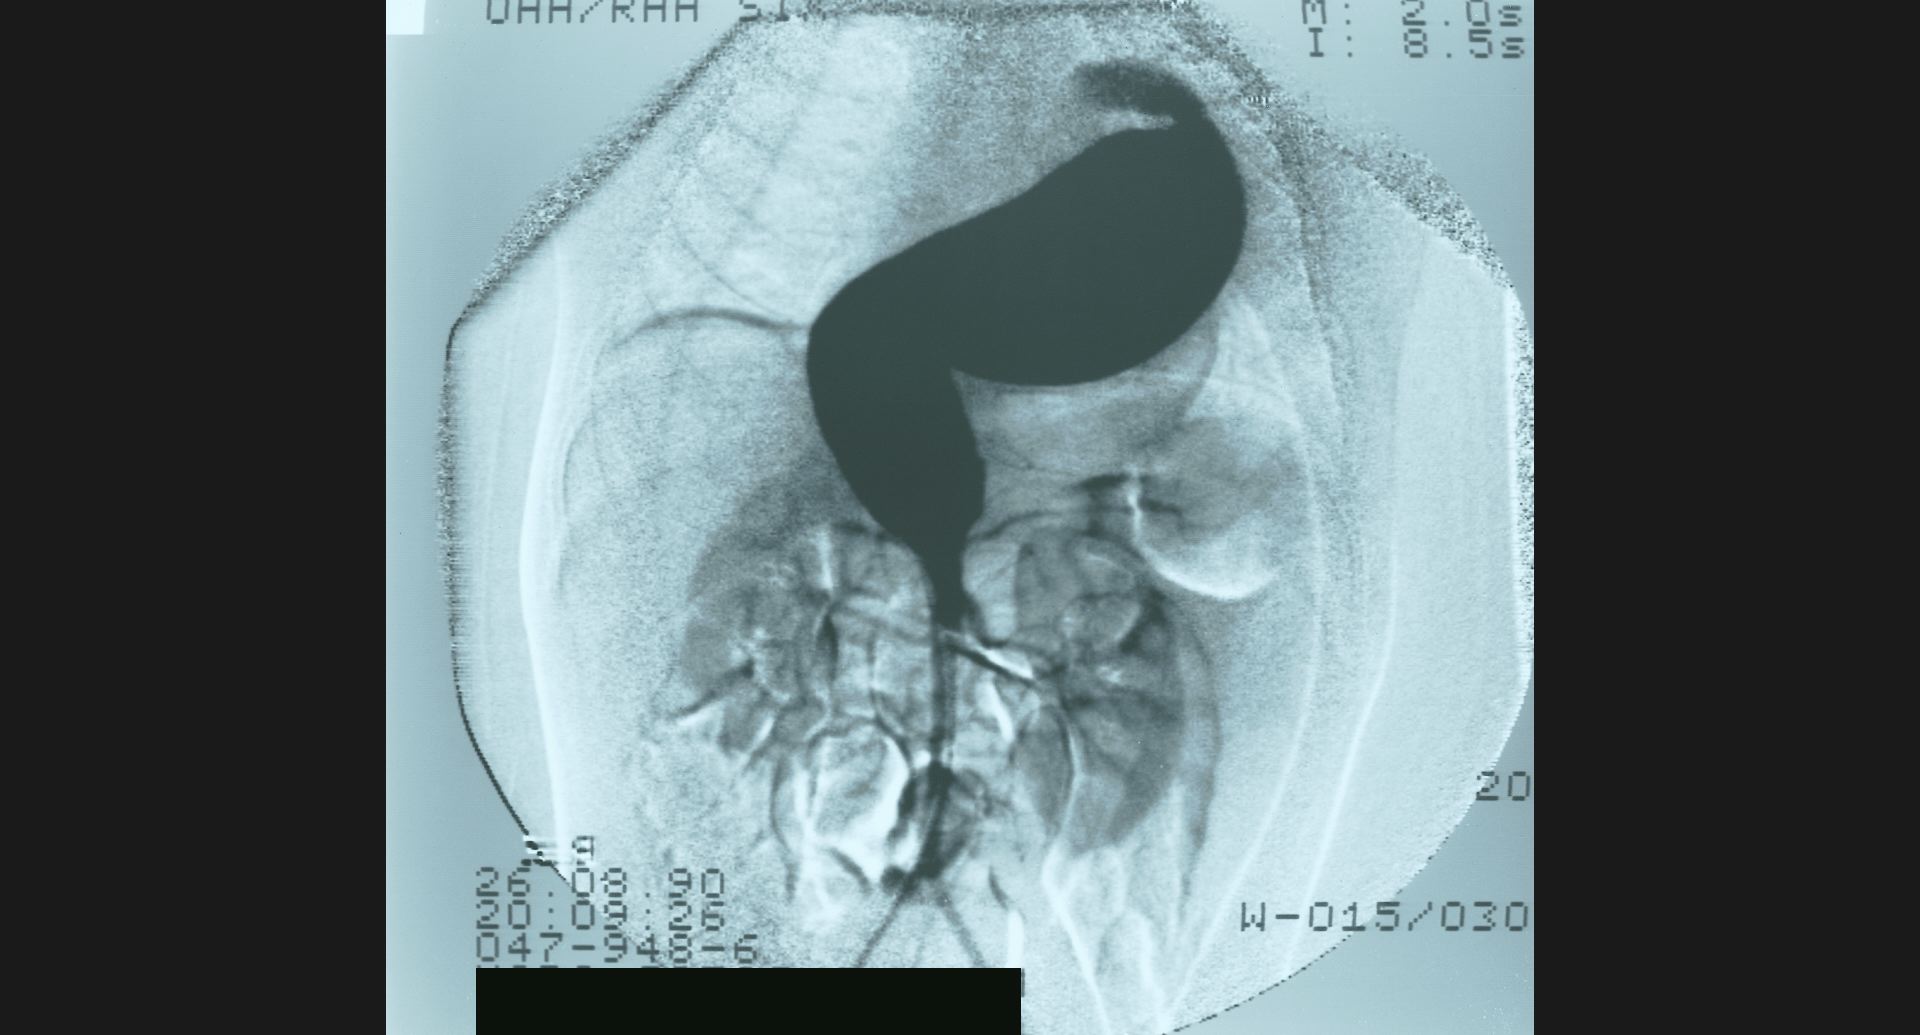

fig.11(59KB) :IVC stenosis (cavography), lateral view

collateral vein。狭窄。